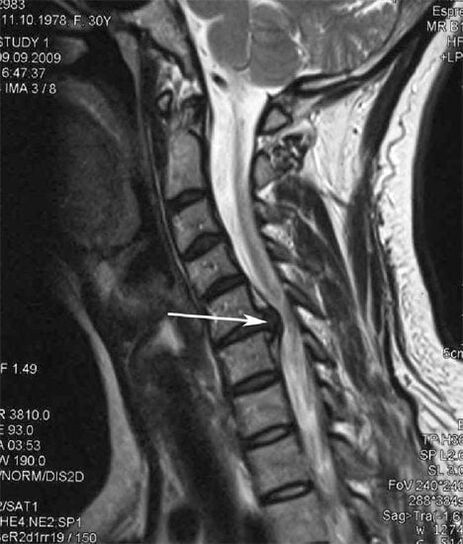

Nos estágios iniciais, a osteocondrose é detectada por ressonância magnética. Mais tarde, a patologia pode ser diagnosticada por meio de radiografia. Nas radiografias da coluna cervical, tornam-se perceptíveis diminuição da distância entre as vértebras, alterações patológicas nas articulações facetárias e osteofitose.

Muitas pessoas reclamam que não conseguem virar o pescoço devido à forte dor que surge após levantar algo pesado repentinamente. Este fenômeno indica a formação de uma hérnia de disco. A causa da dor nas costas, pescoço e membros superiores é a compressão de uma das raízes nervosas que emergem da medula espinhal.